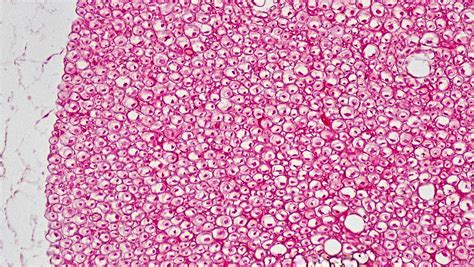

3. Staining: Staining enhances the visibility of different cellular components. Common stains for nervous tissue include:

• Hematoxylin and Eosin (H&E): This stain highlights the nuclei and cytoplasm of cells, providing a general overview of the tissue structure.

• Luxol Fast Blue: This stain is specific for myelin, the insulating sheath around axons, making it useful for studying myelinated nerves.

• Nissl Stain: This stain targets Nissl bodies, which are clusters of ribosomes in the cytoplasm of neurons, helping to identify neuronal cell bodies.